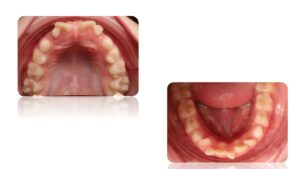

La Classe II Subdivision

La classes II subdivision fonctionnelle est la conséquence d’une mastication préférentielle voir exclusivement unilatérale. Cette dysfonction engendre alors une bascule du plan d’occlusion dans le plan frontal mais également dans le plan vertical et sagittal.

L’orthodontie systémique permet d’appréhender cette pathologie par l’analyse des latéralités mandibulaires (AFMP).

Le traitement qui en découle est donc fonctionnel et stable car il permet une réorientation du plan occlusal, symétrisant ainsi les AFMP et donc la mastication.